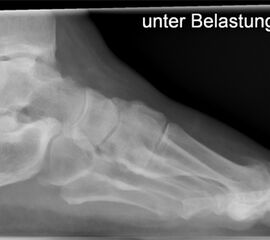

• Belastete Röntgenaufnahmen in 3 Ebenen.

Beim Hallux rigidus Stadium II beobachtet man die Ausbildung von Osteophyten dorsal, medial und lateral sowohl metatarsal als auch an der Basis des Grundphalanx bei noch ausreichender Knorpelbedeckung der plantaren Gelenkabschnitte 12. Diese führen zum Impingement, zur Einschränkung der Extension im Großzehengrundgelenk und konsekutiver Störung des Abrollverhaltens des Fußes.